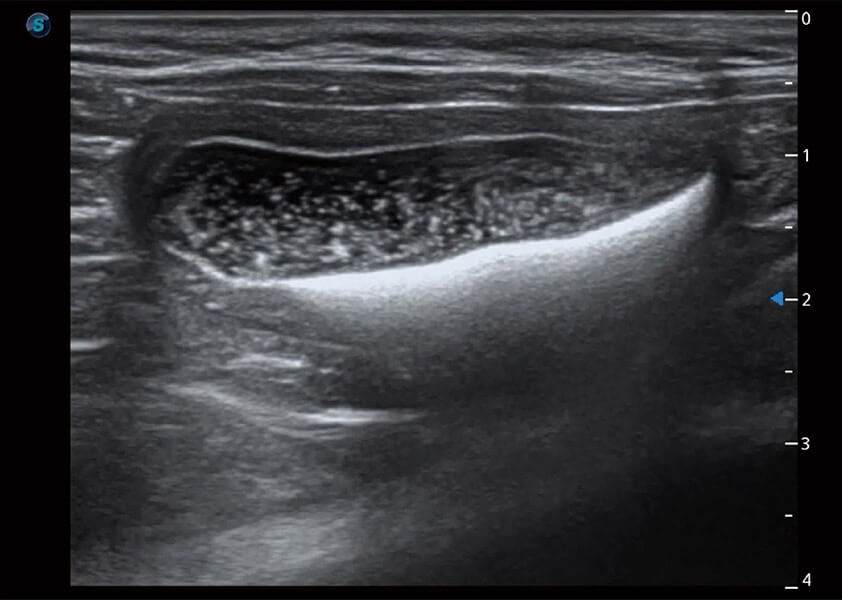

ProPet 60 作為一款高端臺(tái)式動(dòng)物超聲設(shè)備,為動(dòng)物醫(yī)生的日常診斷提供了一系列貼合動(dòng)物臨床需求、解決臨床實(shí)際問(wèn)題的高級(jí)成像功能。憑借全系列高清探頭,滿足醫(yī)生對(duì)腹部、心臟、生殖、淺表、肌骨等成像的所有需求,切實(shí)幫助您提升檢查效率,提高診斷信心。